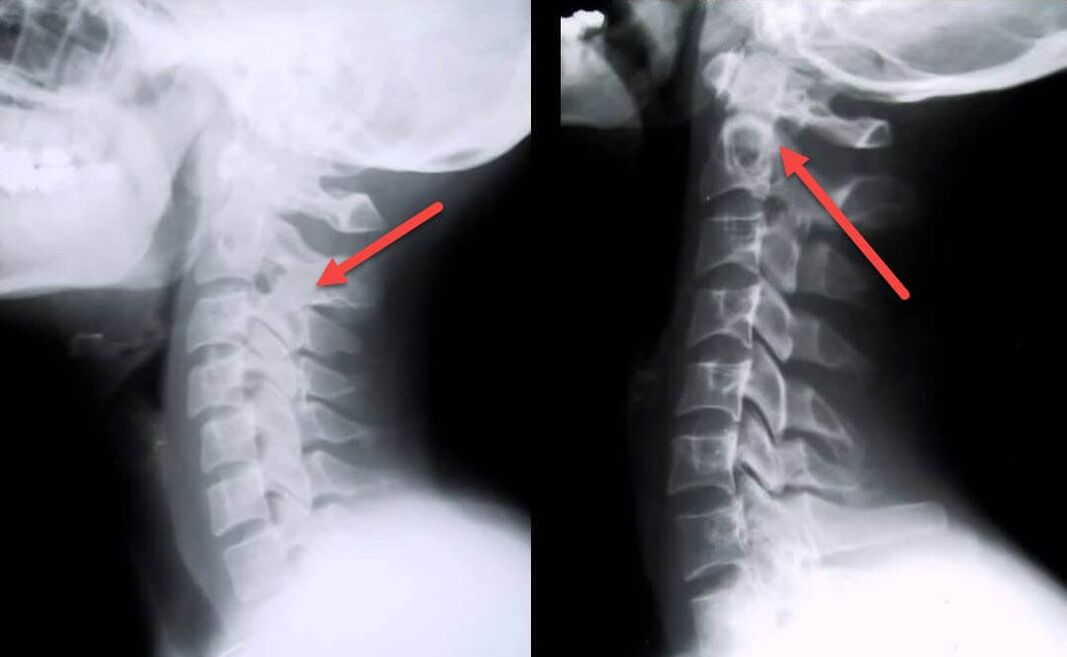

Das aussagekräftigste diagnostische Verfahren ist die Radiographie. Pathologien 1. Grades entsprechen dem 1. oder 2. radiologischen Stadium. Die resultierenden Bilder visualisieren typische Krankheitszeichen.

| Röntgenstadien der zervikalen Osteochondrose 1. Grades | Charakteristische Zeichen |

|---|---|

| Stufe 1 | Kleinere Veränderungen der Krümmung der Wirbelsäule im Halsbereich, die ein oder mehrere Segmente betreffen |

| Stufe 2 | Leichte Verdickung der Bandscheiben, Verformung der Processus uncinatus, Aufrichtung der Lordose, geringfügige Wucherungen der Knochenstrukturen |